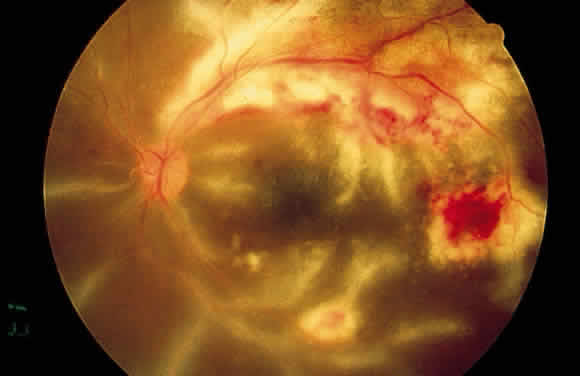

The retinal vessels should be examined for evidence of vasculitis, noting whether the vasculitis affects primarily the veins (phlebitis) or the arteries (arteritis). Patients with sarcoid uveitis commonly have extensive periphlebitis, whereas patients with Behçet's disease may have more of an arteritic picture. Patients with herpetic retinitis may have extensive arteritis and phlebitis, which produce the appearance of “frosted branch angiitis”37 (Fig. 13).